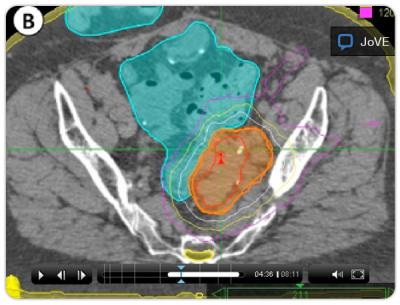

Unlike traditional radiation therapy, SBRT uses focused radiation beams and targets well-defined tumors. In order to focus in on the region, the tumors need to be imaged and marked (using fiduciary markers) in advance. During treatment with the Cyberknife system from Accuray, patients need to be immobilized, and even the movement from the patient's breathing needs to be taken into account.

The highly specific nature of the procedure not only shortens treatment time, it limits the effect of the radiation on healthy tissues.